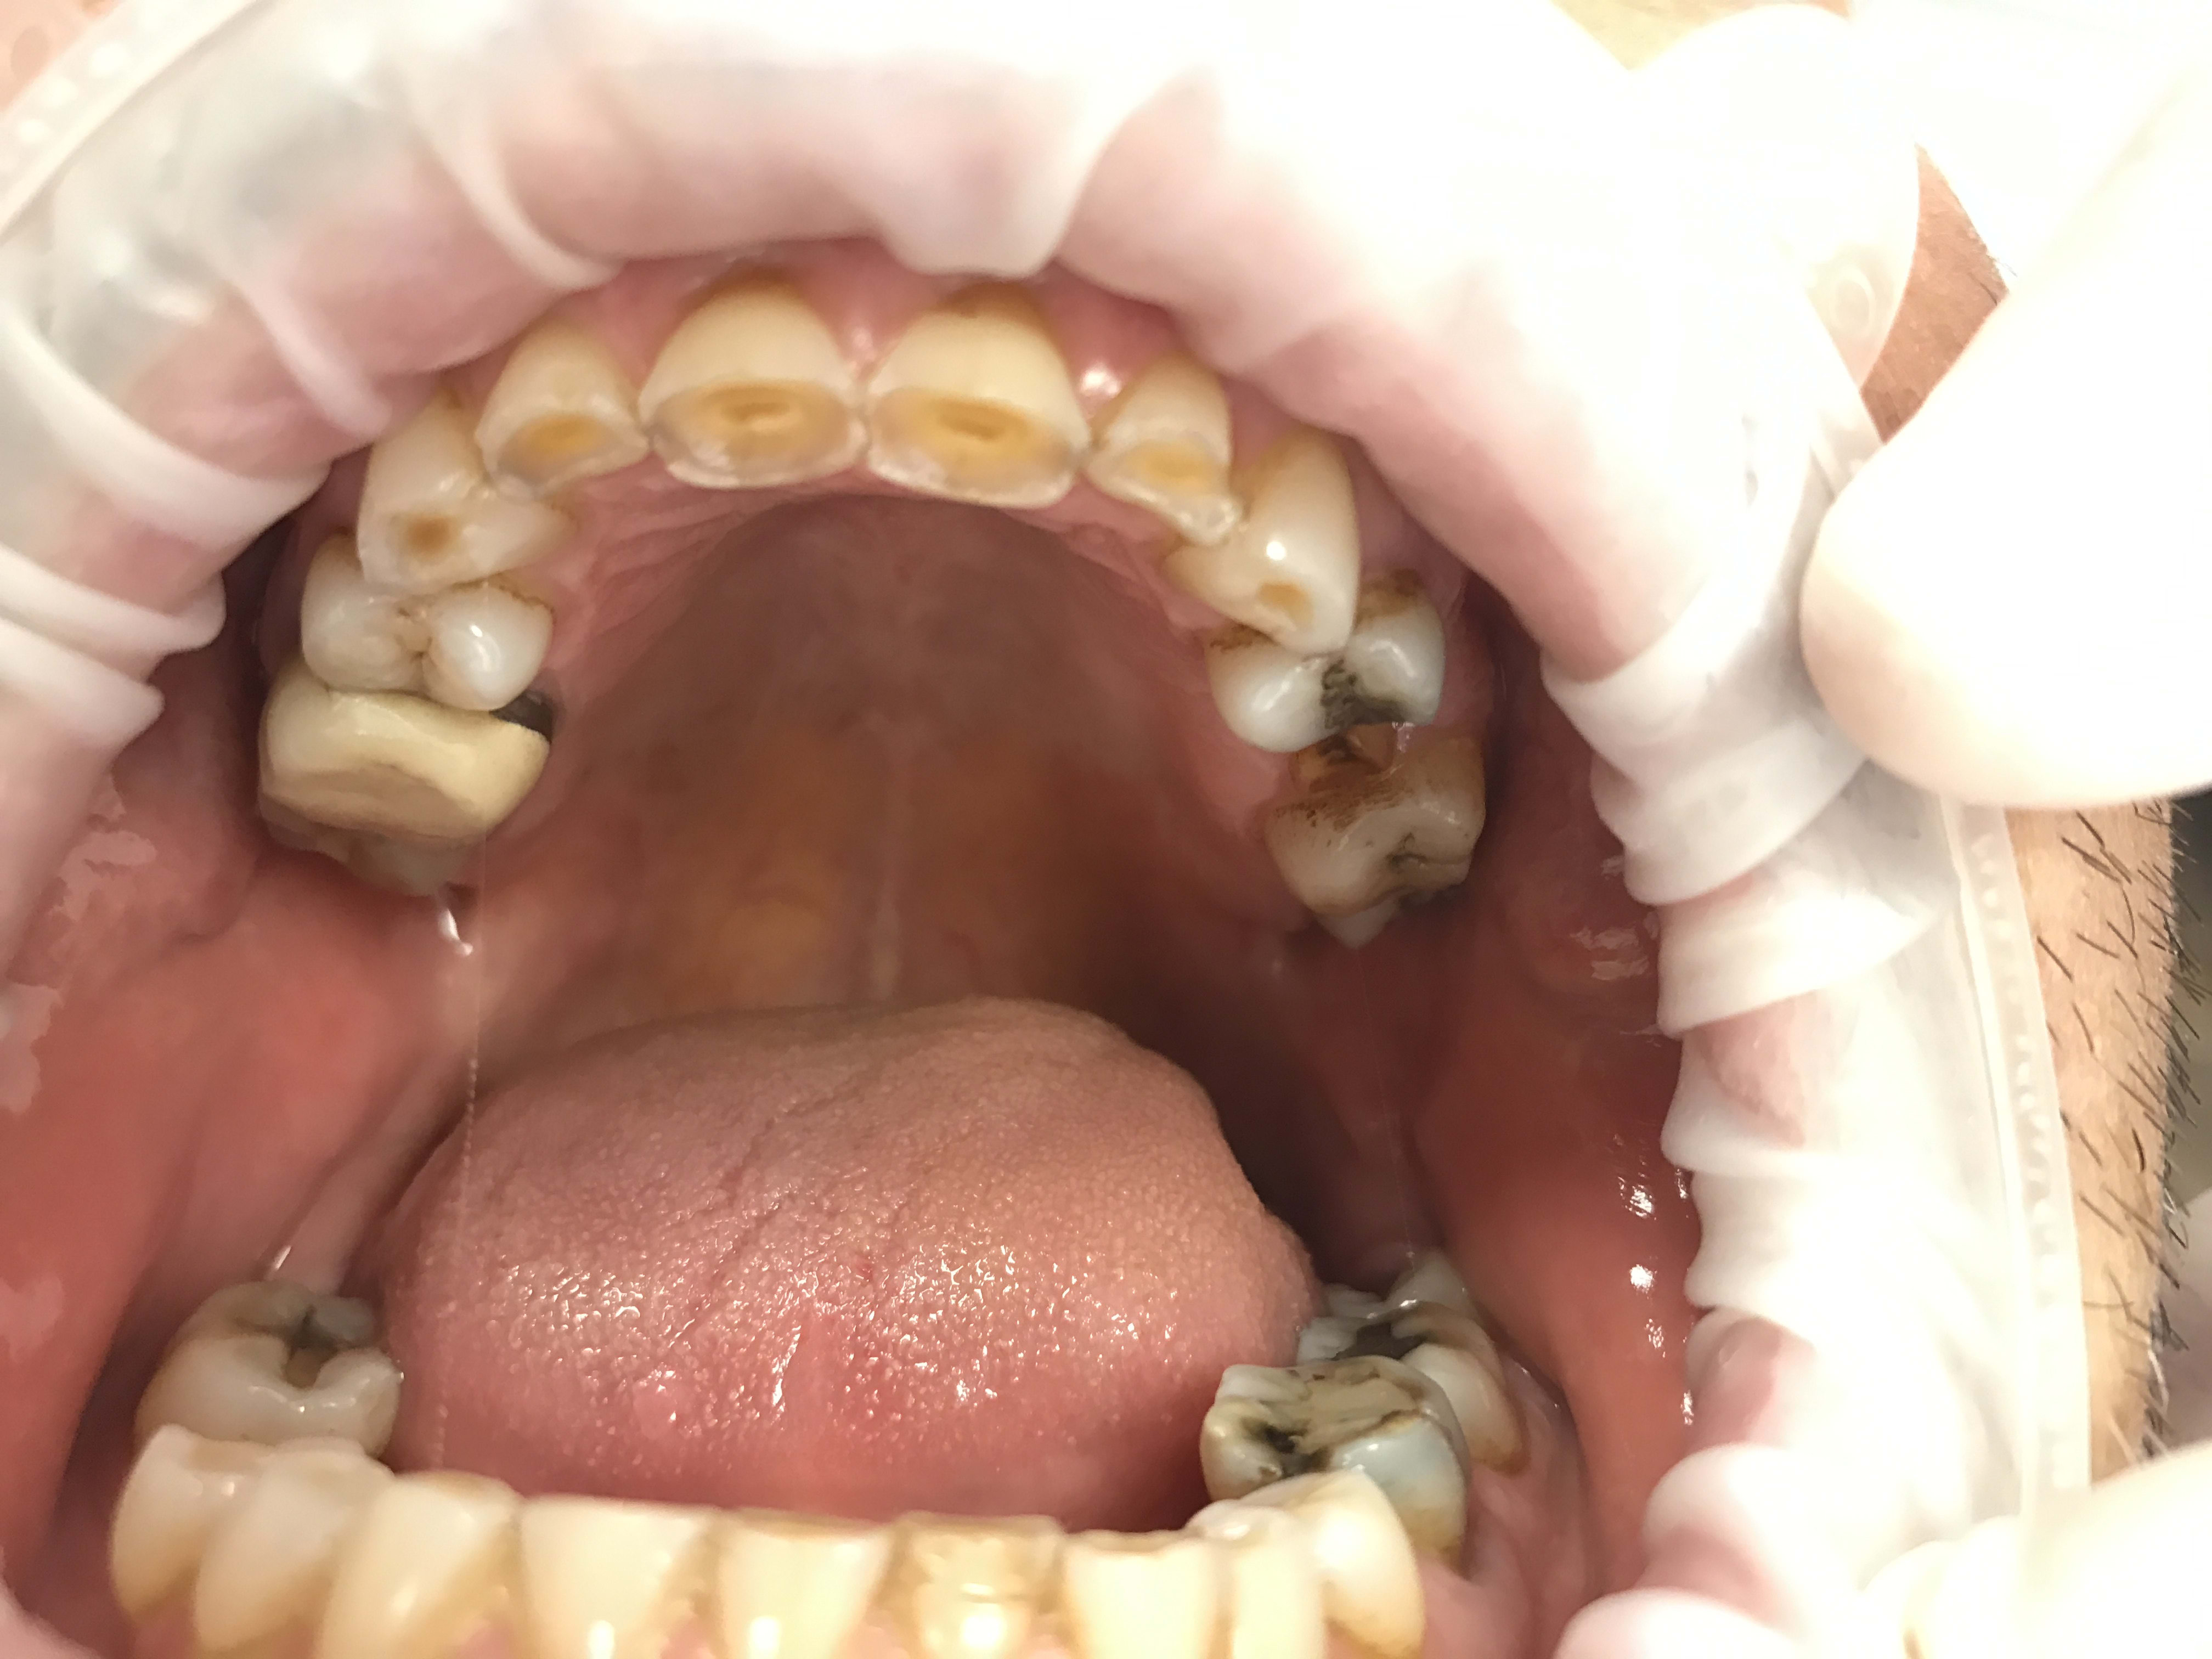

Restauration globale sur un patient qui bruxe?

Un homme de 55 ans, pas de problème de santé à signaler mis à part qu'il soit sourd même si je doute que ça ait une importance quelconque.

Le patient souhaiterait refaire son sourire, et bizarrement il m'en a parlé lui même sans utuliser le terme specifique mais augmenter la DVO.

Cela fait bien longtemps qu'il bruxe et a usé toutes ses dents, n'a plus de calage.

Il y a un retraitement à faire et deux implants à poser (26 46).

Je pensais faire suite au rte et à la pose des implants un wax up mock up avec facettes en antérieure et table top/couronnes en postérieur, et augmentation de la dvo de plusieurs mm.